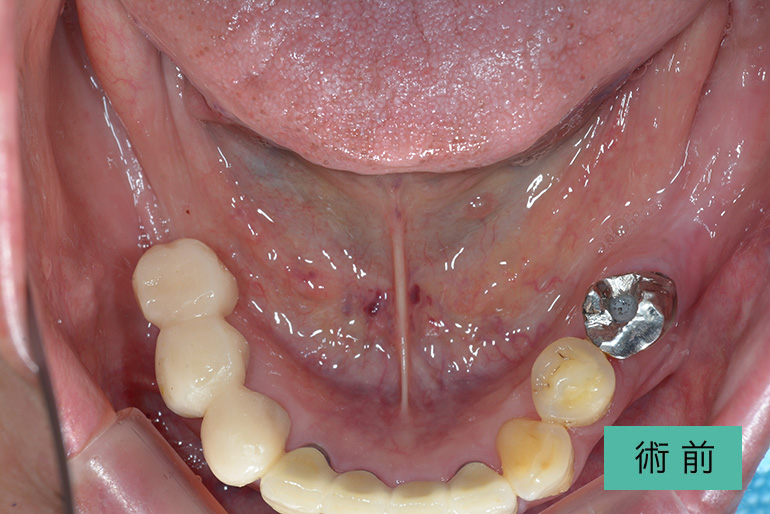

オールセラミック①

| 治療内容 | 上顎インビザライン矯正 右上1番から左上の2番のセラミック冠 上顎前歯の叢生、右上犬歯の捻転の改善のため、上顎のみインビザライン矯正を行なった また、根尖病巣があった為補綴を除去、顕微鏡根管治療を行い、セラミック冠を装着した |

| 治療期間・回数 | 約8ヶ月、15回(インビザライン矯正) 約4ヶ月、6回(補綴治療) |

| 費用(税込) | ¥275,000 (上顎インビザライン矯正) ¥495,000(165,000/1本)(補綴費用) ※自由診療 |

| リスク・副作用 | 疼痛、補綴物の脱落、咬合違和感、破折 |